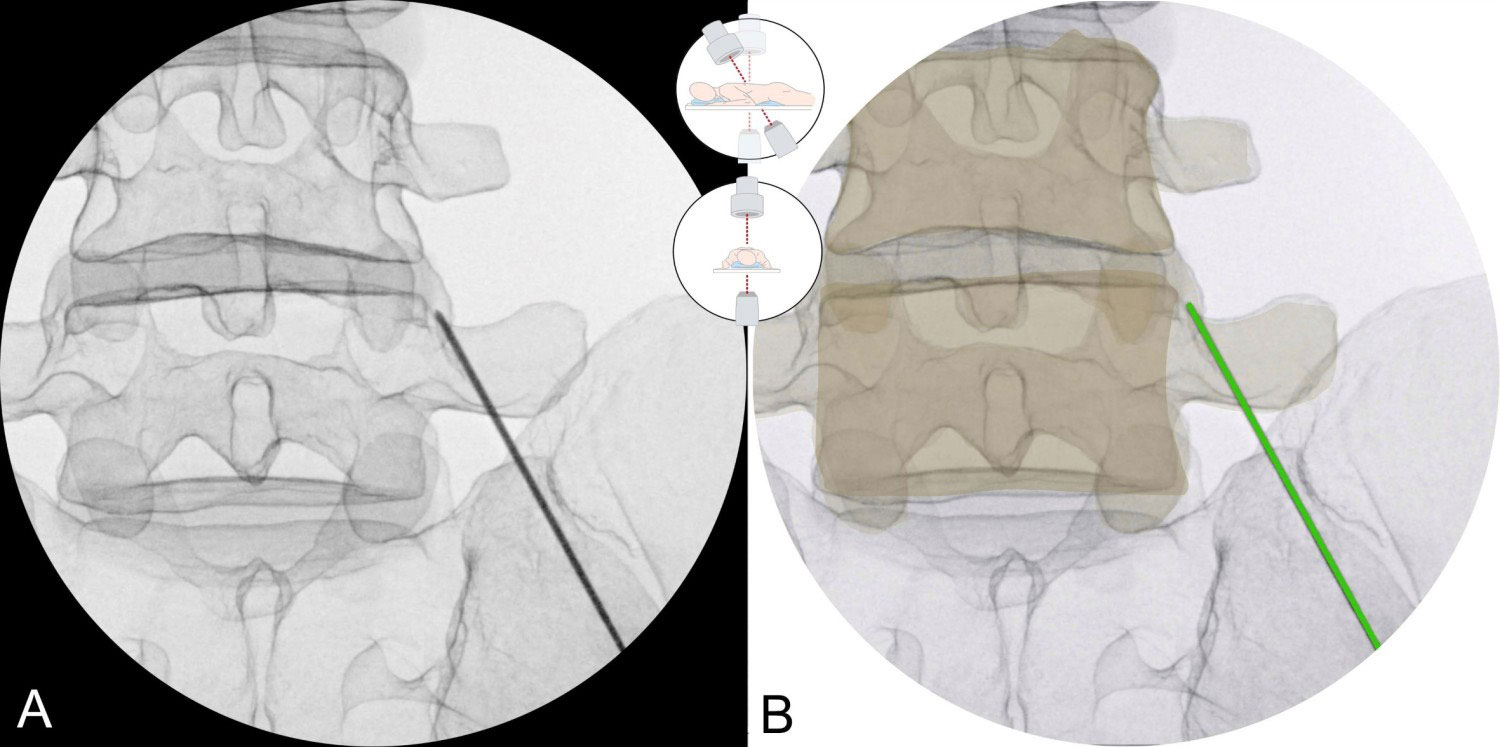

Hierbei werden unter örtlicher Betäubung und unter Bildwandlerkontrolle die Schmerzfasern (Medial Branch) an den arthrotisch veränderten Facettengelenken mit einer Nadelelektrode durch hochfrequenten Strom gezielt erhitzt und verödet bzw. denerviert.